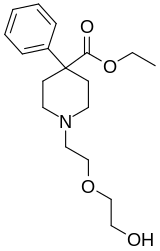

Pirinitramides

Structures

| Pirinitramides | ||||

|---|---|---|---|---|

|

| |||